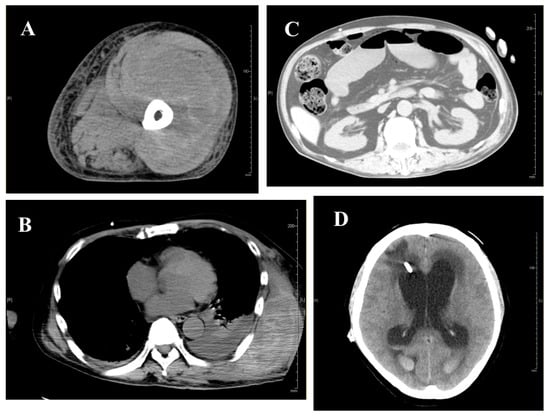

Two and a half months after hospitalization in the Hematology Department, a large subcutaneous hematoma appeared on his left back and chest, complicated by small bowel obstruction (Figure 4 and Figure 5). Eptacog alpha (Ep-α; rhFVIIa, Novo Nordisk, Bagsværd, Denmark) was administered for small intestine resection and massive bleeding. Due to persistent APTT prolongation, emicizumab was administered 3.2 months after hospitalization to achieve stability.

Figure 5.

(A) CT image of a left femoral hematoma at disease onset. (B) CT findings of subcutaneous hematoma and intrathoracic hemorrhage on day 56 after admission. (C) CT image demonstrating strangulated ileus complicated by small bowel perforation, requiring laparotomy on day 80 after admission. (D) CT findings of intracranial hemorrhage on day 102 after admission.